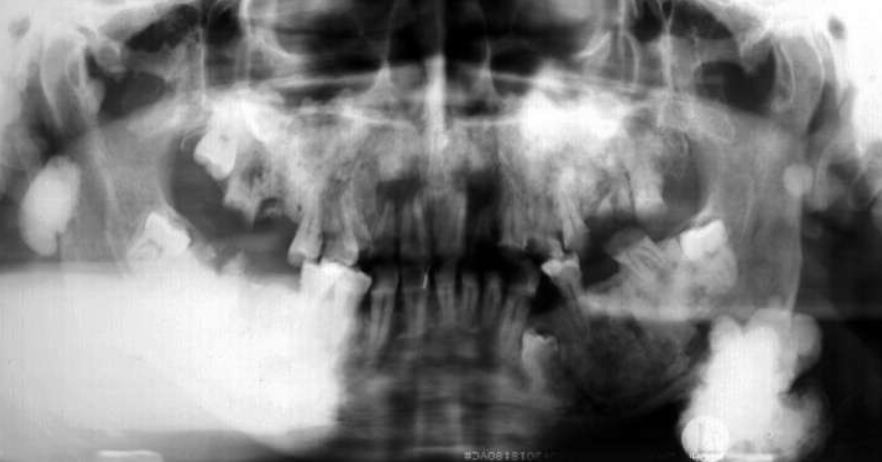

describe what’s occurring in this radiograph

pericoronal/mural; impacted tooth

displacement of #32 + IAN

osseous expansion

thinning of cortices